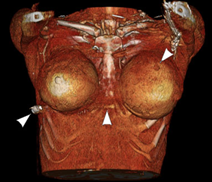

圖三是使用電腦斷層重組的3D立體圖,其中圖片右側的箭頭是子彈的入口,圖片中間的箭頭是子彈行經胸骨前方的位置,圖片左邊的標示是子彈最後停留位置,在病人右外側胸壁上